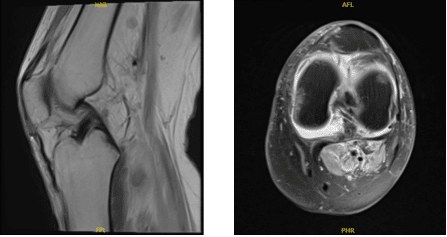

The patient is a 33 year-old female who has been seen in the office for almost six months. She was in a car accident and suffered from pain and edema in her left knee. An MRI revealed a full bucket handle medial meniscus tear into the intercondylar notch.

MRI-3T Left Knee non-contrast

Her pain has been worsening since then and she is not able to extend her knee. She is using an immobilizer and crutches and denies fever or chills. We discussed treatment options including PT, MRI, Injection, surgery and we agreed to go with 3 Tesla MRI and PT to be started as discussed.